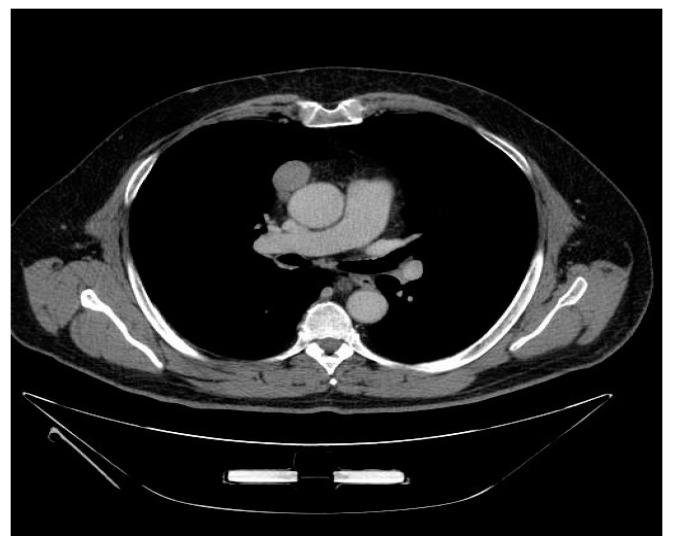

计算机断层扫描参数与外科治疗胸腺瘤的组织学、分期和预后的相关性。

Correlation of Computed Tomography Parameters with Histology, Stage and Prognosis in Surgically Treated Thymomas.

: The histological classification and staging of thymic tumors remains a matter of debate. The correlation of computed tomography (CT) parameters with tumor histology and stage also still has to be completely assessed. The aim of this study was therefore to analyze the correlation of radiological parameters with histological and staging classifications of thymomas evaluating their prognostic role. : Data of 50 patients with thymoma submitted to a complete surgical treatment between 2005 and 2015 were retrospectively analyzed. Tumors were classified according to the WHO and Suster and Moran (S&M) histological classifications and to the Masaoka-Koga and tumor, node and metastases (TNM) staging systems. The correlation of CT features with histology and stage and the prognostic role of histopathological and radiological features were assessed. : Five-year overall (OS) and disease-free survival (DFS) were 90.3% and 81.1%, respectively. A significant correlation of DFS with the Masaoka-Koga ( = 0.001) and TNM staging systems ( = 0.002) and with the S&M ( = 0.02) and WHO histological classifications ( = 0.04) was observed. CT scan features correlated with tumor stage, histology and prognosis. Moderately differentiated tumors (WHO B3) had a significantly higher incidence of irregular shape and contours ( = 0.002 and = 0.001, respectively) and pericardial contact ( = 0.036). A larger tumor volume ( = 0.03) and a greater length of pleural contact ( = 0.04) adversely influenced DFS. The presence of pleural ( < 0.001) or lung invasion ( = 0.02) and of pleural effusion ( = 0.004) was associated with a significantly worse OS. : Pre-operative CT scan parameters correlate with stage and histology, and have a prognostic role in surgically treated thymomas.

摘要

胸腺肿瘤的组织学分类和分期仍然存在争议。计算机断层扫描(CT)参数与肿瘤组织学和分期的相关性也仍有待完全评估。因此,本研究旨在分析影像学参数与胸腺瘤组织学和分期分类的相关性,评估其预后作用。

回顾性分析了 2005 年至 2015 年间接受完全手术治疗的 50 例胸腺瘤患者的数据。肿瘤根据世界卫生组织(WHO)和 Suster and Moran(S&M)组织学分类以及 Masaoka-Koga 和肿瘤、淋巴结和转移(TNM)分期系统进行分类。评估了 CT 特征与组织学和分期的相关性,以及组织病理学和影像学特征的预后作用。

5 年总生存率(OS)和无病生存率(DFS)分别为 90.3%和 81.1%。DFS 与 Masaoka-Koga( = 0.001)和 TNM 分期系统( = 0.002)以及 S&M( = 0.02)和 WHO 组织学分类( = 0.04)显著相关。CT 扫描特征与肿瘤分期、组织学和预后相关。中度分化肿瘤(WHO B3)更常出现不规则形状和轮廓( = 0.002 和 = 0.001)和心包接触( = 0.036)。较大的肿瘤体积( = 0.03)和更大的胸膜接触长度( = 0.04)对 DFS 有不利影响。存在胸膜( < 0.001)或肺侵犯( = 0.02)和胸腔积液( = 0.004)与 OS 显著相关。

术前 CT 扫描参数与分期和组织学相关,对手术治疗的胸腺瘤具有预后作用。